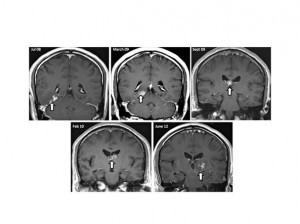

Ahimè, no. Ci sono stati altri casi simili in passato. Un uomo, in Gran Bretagna, ha vissuto per quattro anni con un verme parassita sempre nel cervello, preso mangiando crostacei e rane cinesi. Risultato? Forti mal di testa e un olfatto alterato. La tenia, lunga ben un centimetro, si era fatta strada, sino a che i medici dell’ospedale Addenbroke di Cambridge si sono resi conto della presenza del parassita, con una risonanza al cranio.